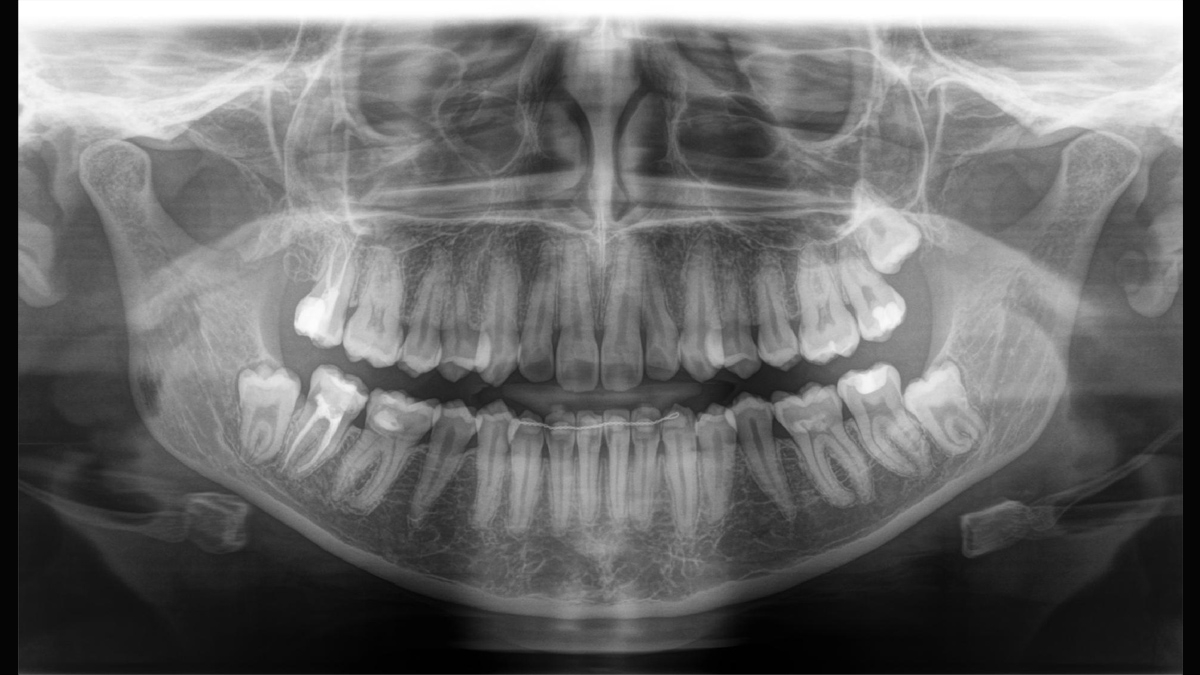

Orthophos SL é o mais novo membro da bem-sucedida família de imagens 2D da Dentsply Sirona. Ele ganha pontos por funcionalidade, qualidade e design. Com seu sensor DCS e tecnologia SL, a unidade de imagem Orthophos SL 2D satisfaz até as maiores necessidades em relação a imagens panorâmicas.

Junto com o software de imagem pioneiro Sidexis 4, o Orthophos SL lhe dá acesso a uma variedade de soluções inovadoras de tratamento. A segurança do investimento é garantida: Orthophos SL 2D pode ser equipado com um braço cefalométrico ou um sensor 3D com um volume de até 11cm x 10cm a qualquer momento.